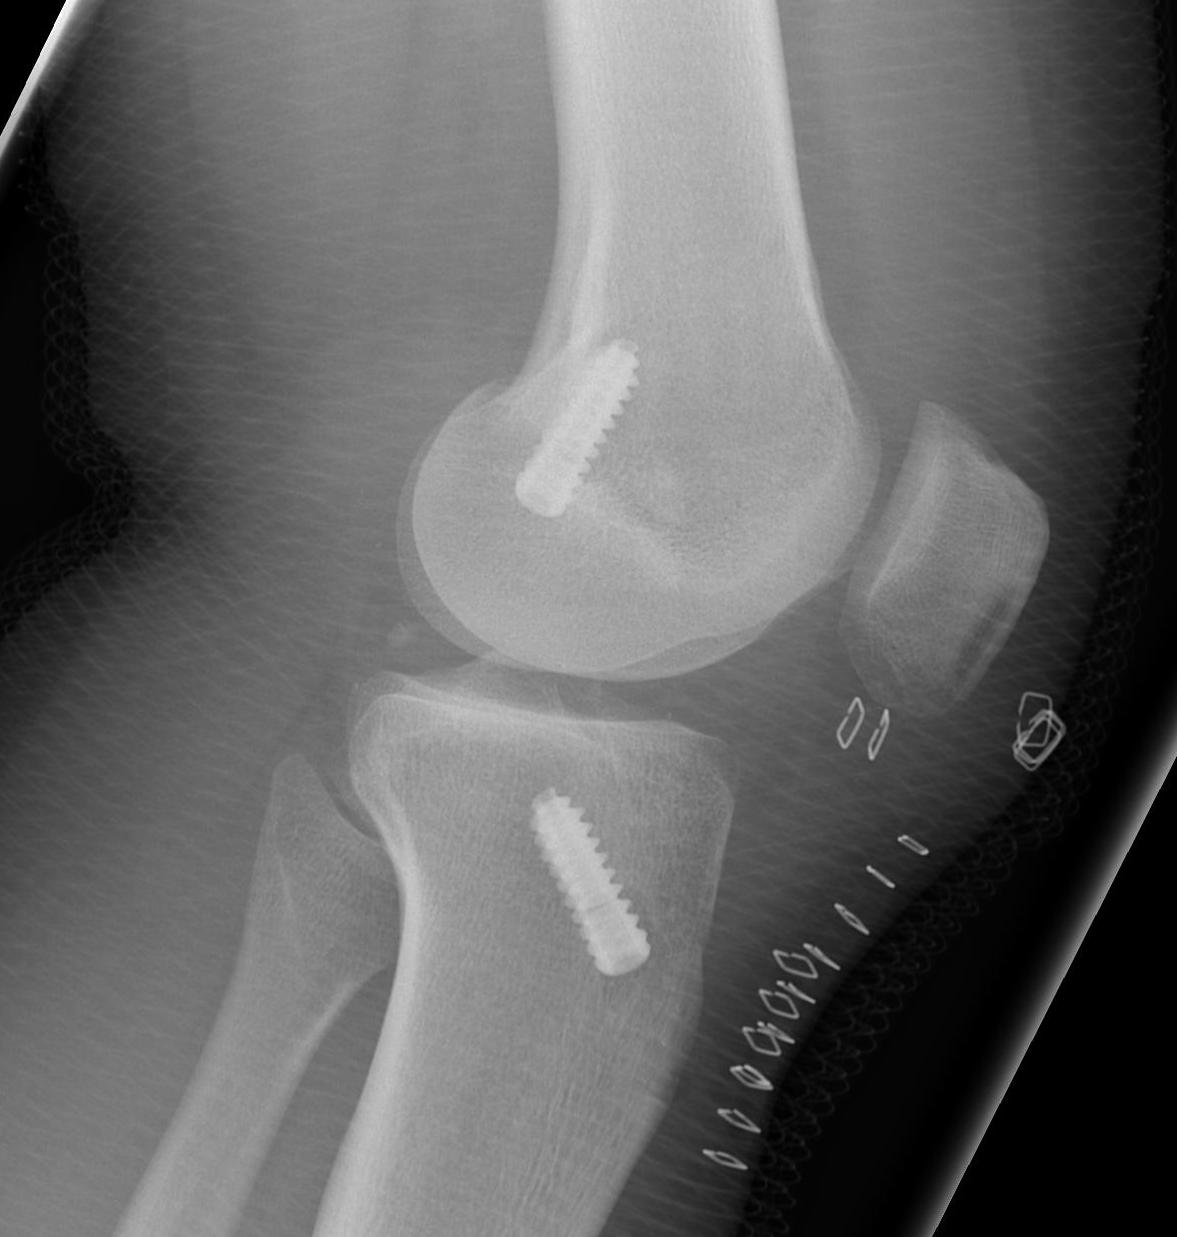

Post Op xrays